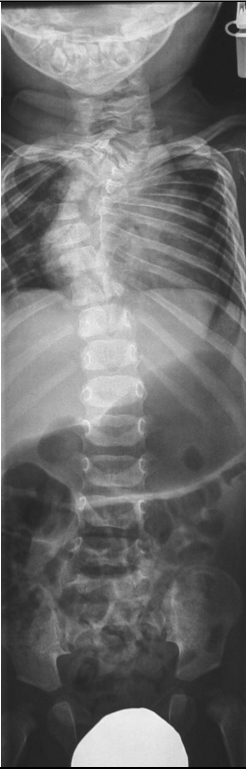

Anteroposterior cervico-thoracic radiograph showed partial vertebral body and defective ossification of the cervico-thoracic pedicles associated with ill-defined fused hemivertebrae along T1/5 (Figure 1 [Fig. 1]).

Figure 1: Anteroposterior cervico-thoracic radiograph showed partial vertebral body and defective ossification of the cervico-thoracic pedicles associated with ill-defined fused hemivertebrae along T1/5.